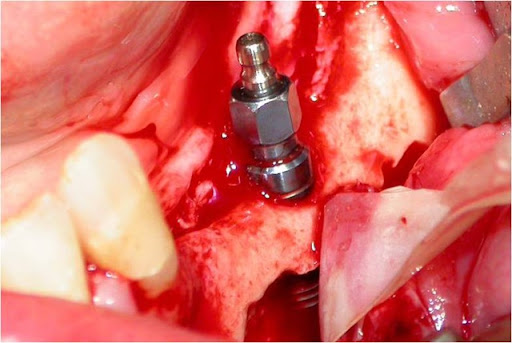

As osteotomias são demarcadas com brocas esféricas pequenas e a seguir, completadas com brocas fenestradas ou serras reciprocantes e oscilantes, descolando-se a cortical vestibular com cinzéis delicados. A remoção do osso medular e da parede do canal mandibular realiza-se com curetas delicadas. A manipulação do NAI exige o uso de instrumentos de contorno suaves e tiras de látex (35) (Figs. 5, 6 e 7).

O tamanho e a localização das osteotomias irá depender da técnica adotada. A transposição do NAI consiste numa osteotomia ao redor do forame mentoniano, removendo-o e, a seguir, a confecção de uma janela óssea posterior seguindo o trajeto do canal mandibular (25).

Figs. 5, 6 e 7 - A osteotomia completa com a remoção da medular. Essa remoção do osso medular e da parede do canal mandibular realiza-se com curetas delicadas. A manipulação do NAI exige o uso de instrumentos de contorno suaves e tiras de látex, com sua transposição.

Figs. 8, 9 e 10 - Os implantes já perfeitamente fixados, com a suave deposição do plexo alveolar inferior na sua loja cirúrgica.

Uma vez localizado o canal mandibular sua parede é cuidadosamente retirada, liberando-se progressivamente o feixe neurovascular. Eventualmente, por uma outra técnica há necessidade de se realizar a transposição do nervo incisivo para se obter um afastamento satisfatório do NAI. Após o afastamento do feixe, realiza-se a fixação dos implantes, seguindo o protocolo correspondente, utilizando-se da cortical basal ou não, para obter uma melhor estabilidade inicial (24, 30) (Figs. 8, 9 e 10). Na seqüência o NAI é acomodado passivamente na loja óssea quando apenas lateralizado (12, 29).